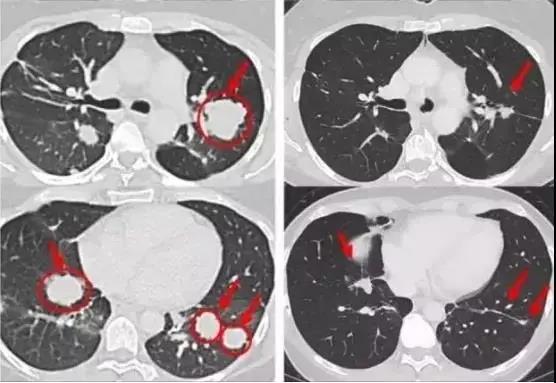

Melinda的肿瘤迅速缩小或几乎完全消失